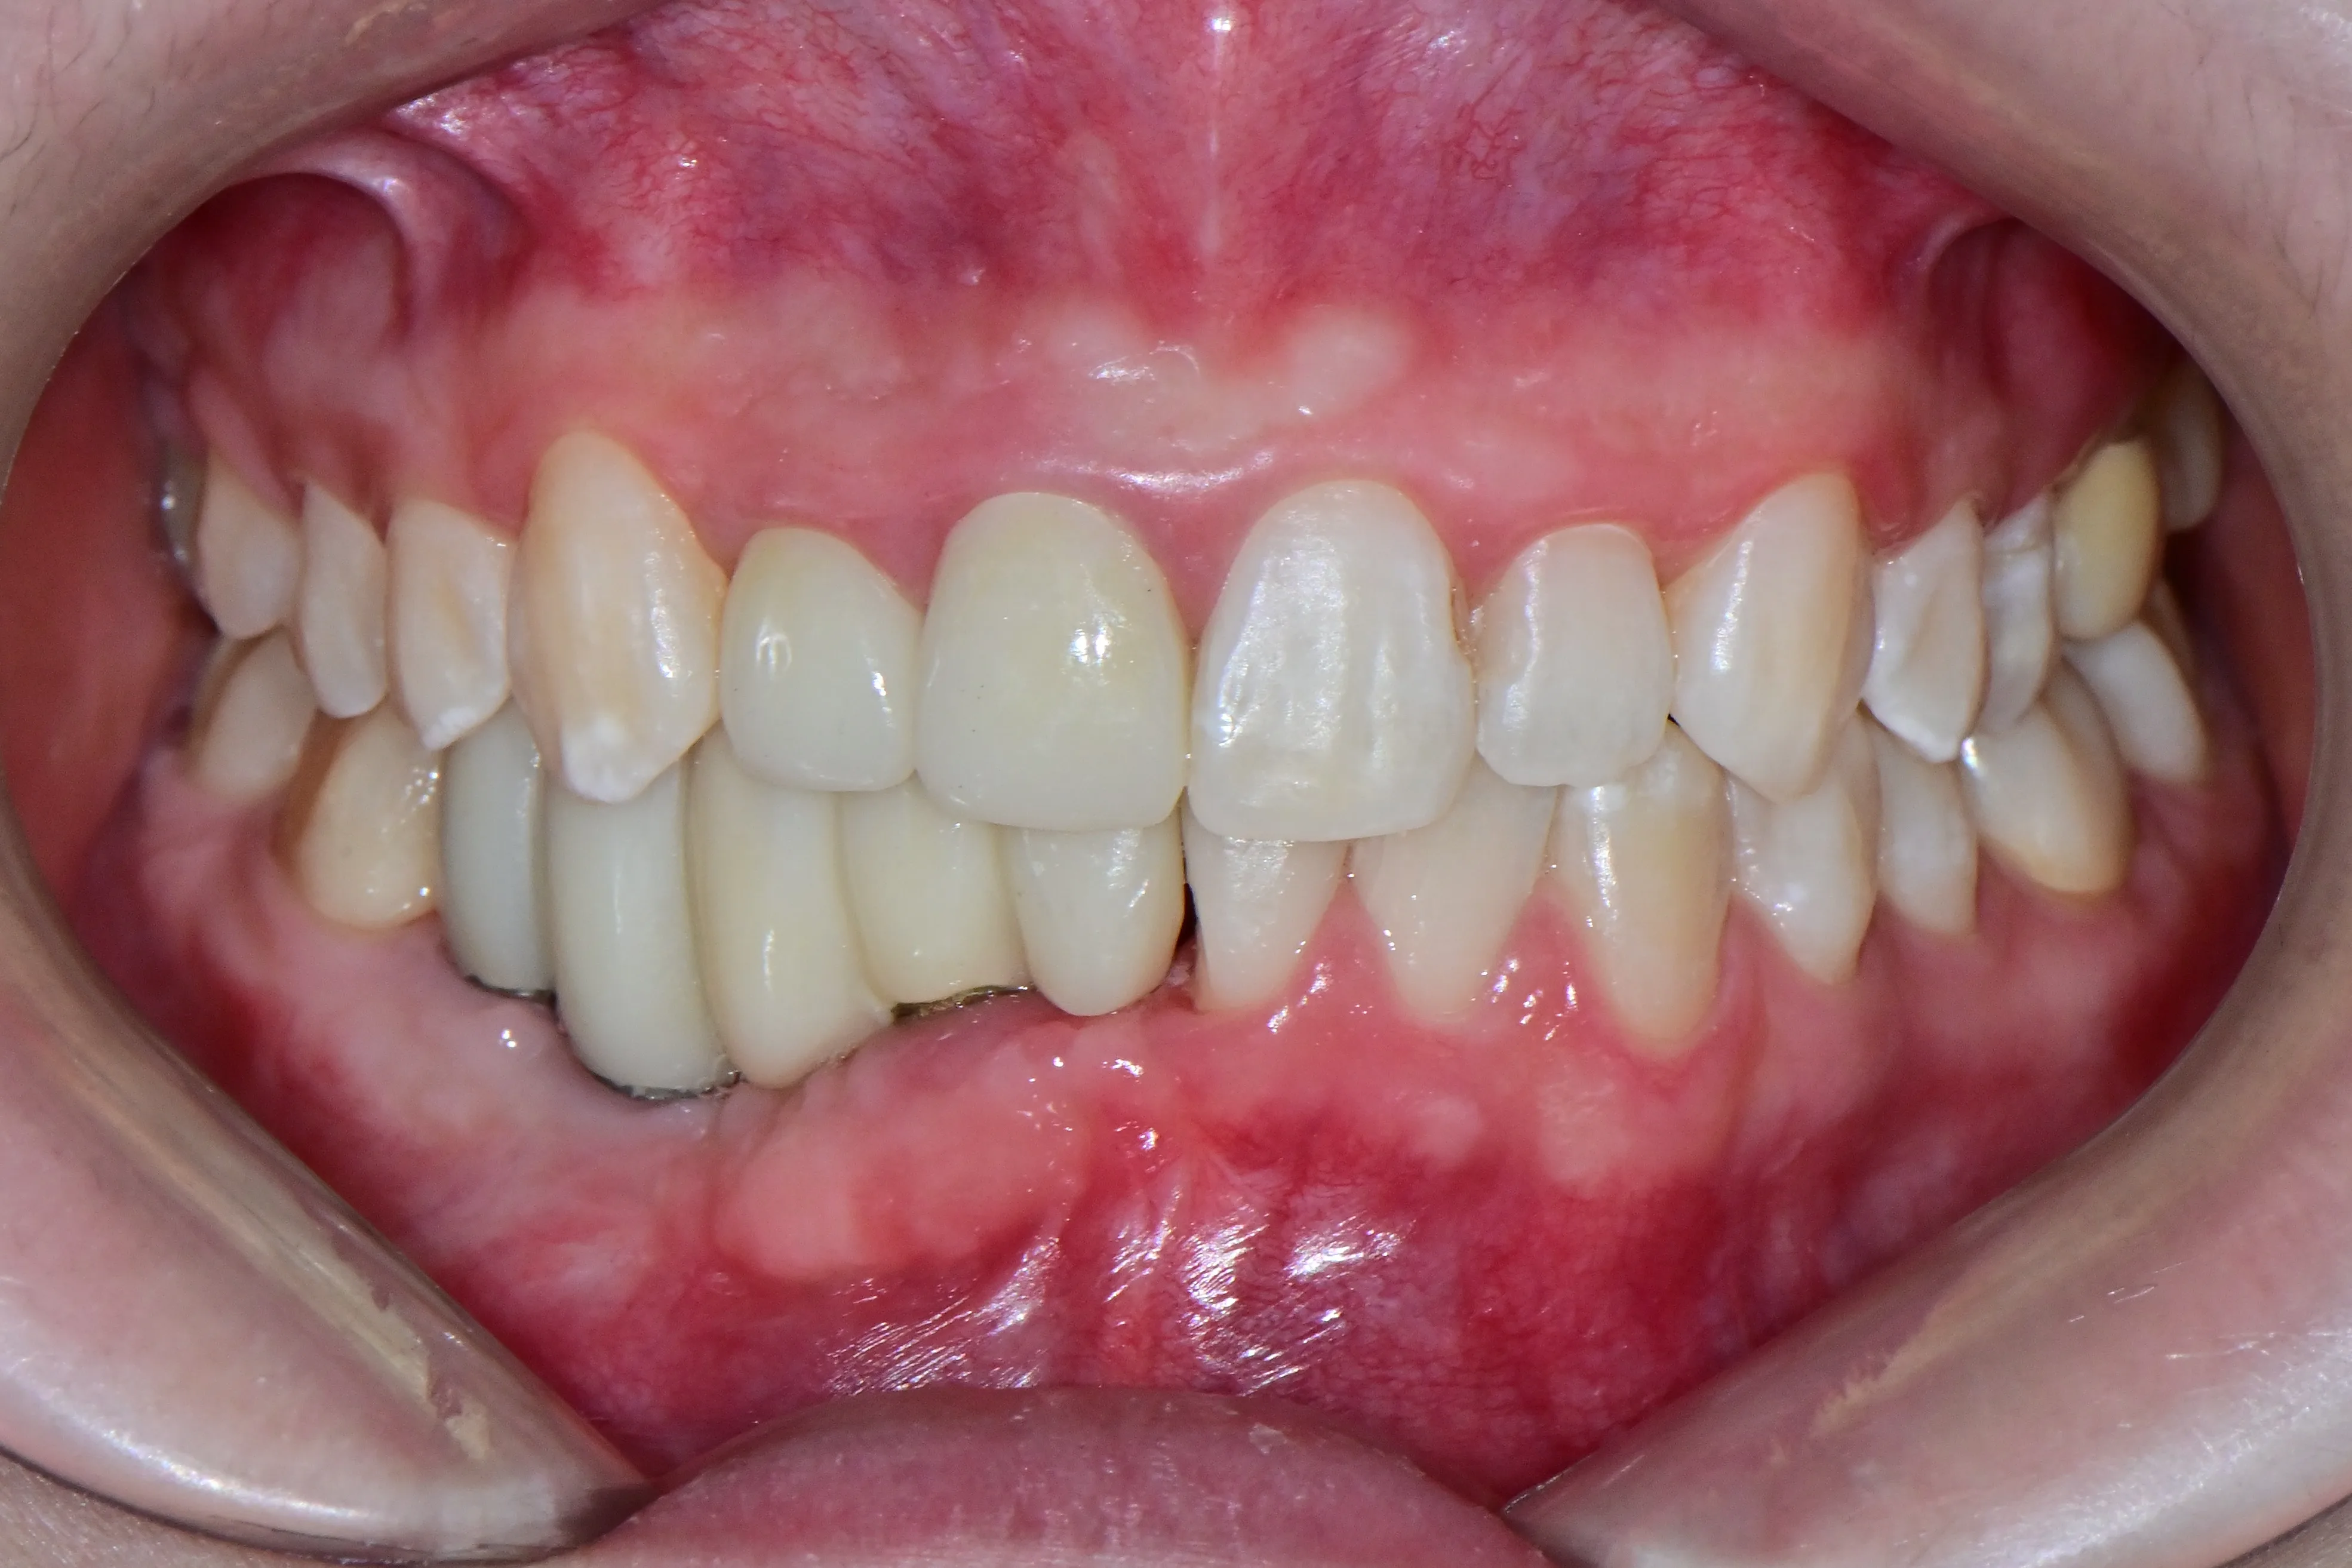

만 21세 환자로, 기존에 사고로 여러 치아를 다치고 상실한 상태로 매우 심한 교합무너짐이 있었습니다.

치료전 (Before)